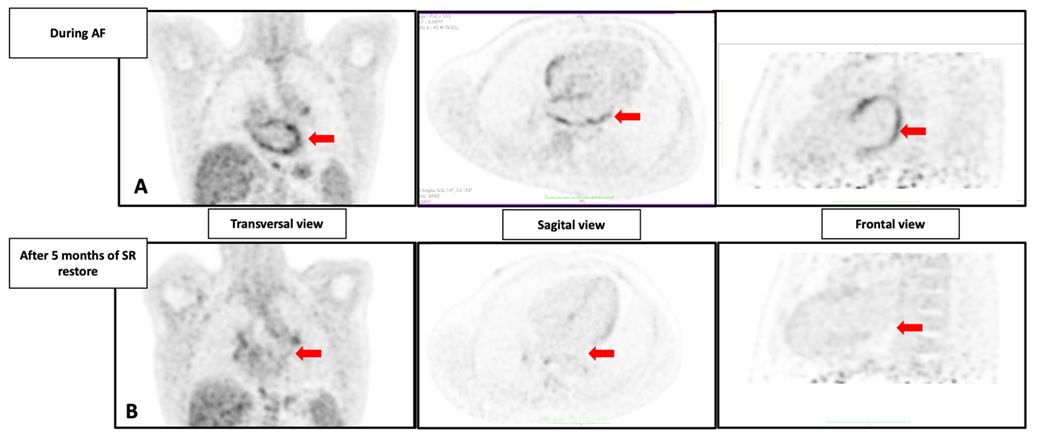

| Figure 1: Two Dimension 18F-FDG uptake performed in patient during Atrial Fibrillation (AF) and 5 months after sinus rhythm (SR) restoration: PET imaging in transversal, sagittal, frontal view (A) and A-P view (B) shows a decrease of the 18F-FDG uptake after 5 months of SR. Quantification of Left Atrial 18F- FDG uptake using MIM software. Exams and analysis performed with same contrast scale, same patient preparation, same image acquisition, same image preprocessing. The arrows points toward specific heart structures.LA: Left Atrium. |

Cardiac sarcoidosis was suspected, and an 18F-FDG PET was performed prior to pharmacological cardioversion, following European and American nuclear medicine guidelines. The patient received a high-fat, low-carbohydrate meal before the PET, followed by 12 hours of fasting. The images showed excellent suppression of ventricular myocardial 18F-FDG uptake (SUVmean LV wall 0.96, LV cavity 1.40), indicating proper preparation. No focal 18F-FDG uptake was observed in the ventricular wall, excluding active cardiac sarcoidosis. However, diffuse 18F-FDG uptake was seen in both atrial wall (right atrium SUVmean 3.44, interatrial septum 2.66, left atrium 3.35). See figure 1 and table 1.

A follow-up 18F-FDG PET after 5 months of sinus rhythm, with the same dietary preparation, showed complete resolution of atrial wall 18F-FDG uptake (SUVmean 1.09). Mild 18F-FDG uptake was noted in the left ventricular wall (SUVmean of 1.98 vs SUVmean in the LV cavity of 1.16), indicating suboptimal myocardial suppression (see figure 1). The atrial SUVmean was equal to background levels.

This case describes a significant change in FDG uptake in the atrial wall in the same patient following cardioversion for atrial fibrillation (AF). We demonstrated that 18F-FDG PET, performed just before pharmacological cardioversion for persistent AF, revealed markedly increased tracer uptake in the atrial wall compared to the ventricular wall. A follow-up 18F-FDG PET scan, performed under similar conditions after 5 months of sinus rhythm, showed that this metabolic activity in the atrial wall had disappeared.